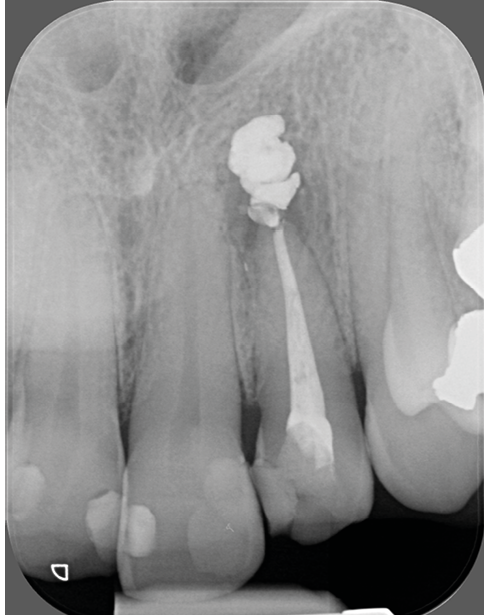

- un retraitement orthograde présente un mauvais rapport bénéfice-risque : par exemple, la présence d’un tenon dont la dépose pourrait fracturer la dent (fig. 2a-b) ;